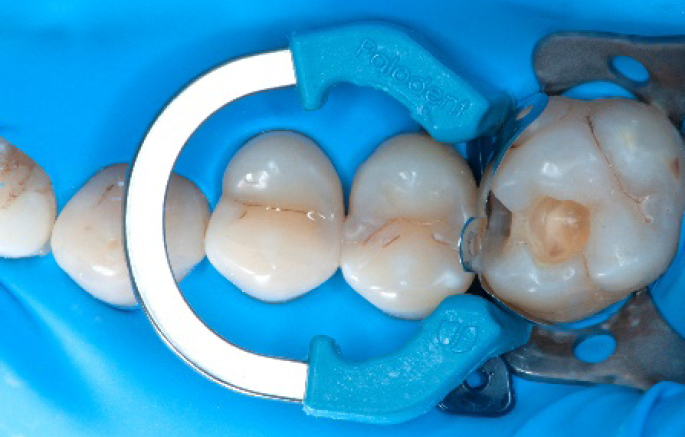

Step 4:

The complete Palodent1 system in place: sectional matrix, wedge and ring.

Step 5:

Buccal view of the Palodent1 system.